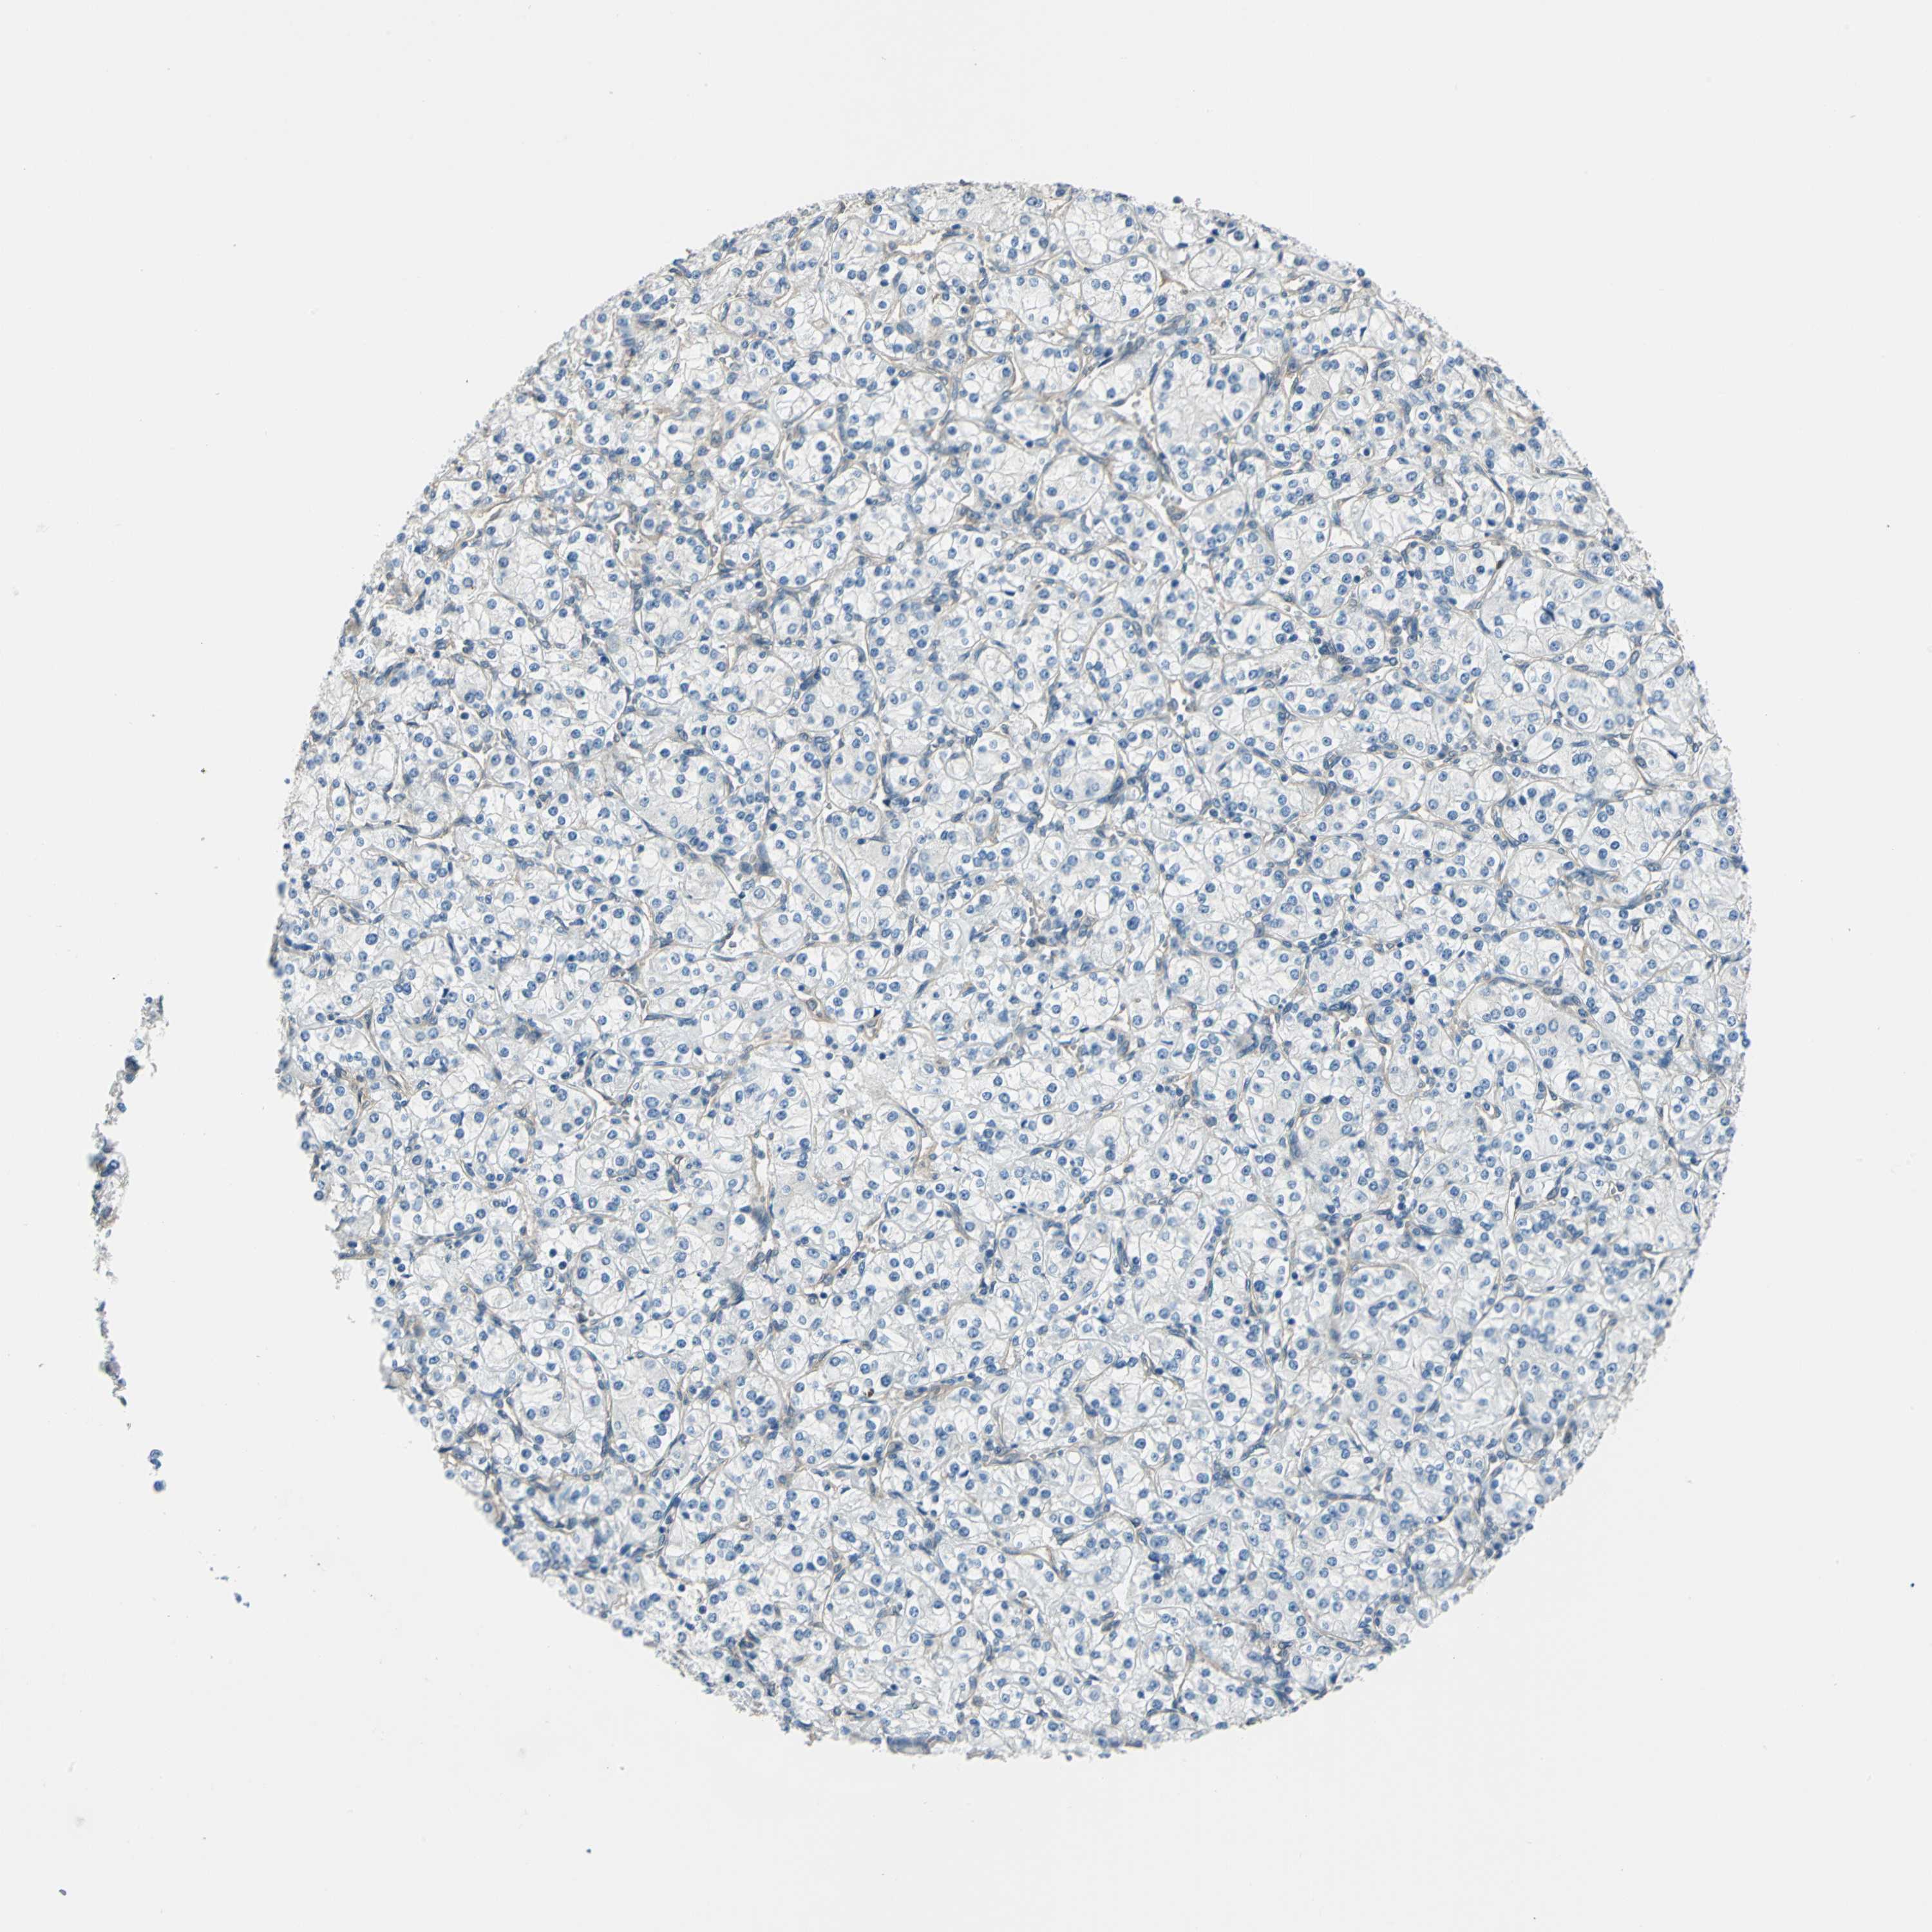

Renal cancer

Kidney renal clear cell carcinoma